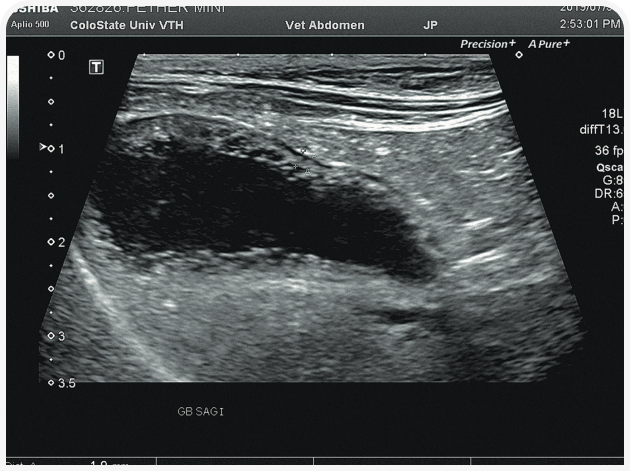

Решающее значение для диагностики и лечения в этом случае будет иметь ультразвуковое исследование органов брюшной полости (Рисунок 6). Диагностику триадита у кошек облегчают визуализация поджелудочной железы и определение толщины/архитектоники стенки кишечника; изменения в паренхиме печени по-прежнему остаются неспецифичными, но изменения в желчном пузыре, скорее всего, помогут установить диагноз. При нейтрофильном холангите у кошки результаты визуализации желчных путей могут оказаться нормальными, но во многих случаях стенка желчного пузыря будет утолщенной и неровной, даже зубчатой (Рисунок 7) (22). Возможны осадок (Рисунок 8) или наличие камней в желчном пузыре, поэтому желчевыводящие пути важно просмотреть до двенадцатиперстной кишки, чтобы исключить внепеченочную окклюзию желчных протоков. Во многих случаях общий желчный проток оказывается перекрыт. Возможен асцит, и в этом случае оправдано проведение аспирации и анализа состава жидкости.

Аспирация содержимого желчного пузыря (чрескожный холецистоцентез под контролем ультразвукового исследования) для цитологического и культурального исследования чаще всего позволяет поставить диагноз и подобрать лечение (Рисунок 9) (23). Если желчный пузырь при визуализации выглядит патологически (например, толщина стенки >1 мм, контур стенки неровный или зубчатый или выраженное гиперэхогенное содержимое (осадок; Рисунок 10), результаты цитологического исследования и бактериального посева, скорее всего, также будут отклоняться от нормы (22,24). Обратите внимание, что при аспирации существует риск разрыва стенки желчного пузыря и/или утечки содержимого с развитием желчного перитонита, но под контролем опытного специалиста УЗИ и при спокойном поведении/седации пациента проблемы возникают редко. Тем не менее если стенка желчного пузыря выглядит эмфизематозной, риск значительно возрастает и вместо аспирации следует рассмотреть возможность хирургического удаления или пробное лечение.